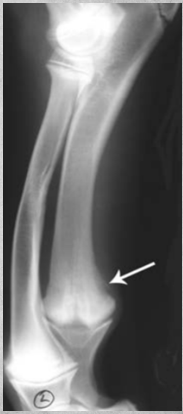

Describe Premature closure of growth plate.

e.g. distal ulna such as in image

results in growth discrepancy and may disrupt the function of the joint

What does this depict?

Premature closure of growth plate distal radius.